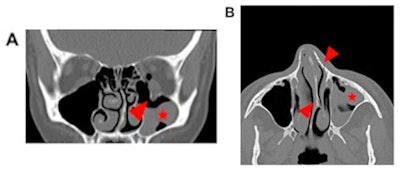

Case 1: A 42-year-old female presenting with diplopia after she reported having been punched by her partner in the face. Head CT revealed a left orbital floor fracture (arrowhead, A), blood-filled left maxillary sinus (asterisk, A, B), and nasal bone fractures as well as a nasal septum fracture (arrowhead, B) with deviation of the nasal septum to the left (arrowhead, B). The patient initially reported that she had run into a cupboard. Careful questioning indicated that she was attacked by her life partner. A social worker and, later, the police were informed. Images and caption courtesy of European Radiology.